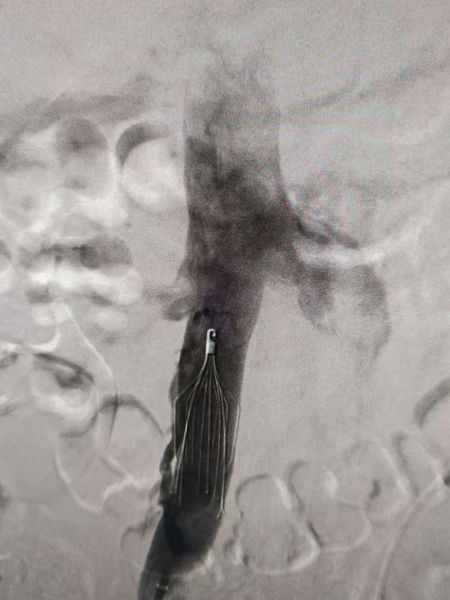

预防血栓脱落下腔静脉滤器植入